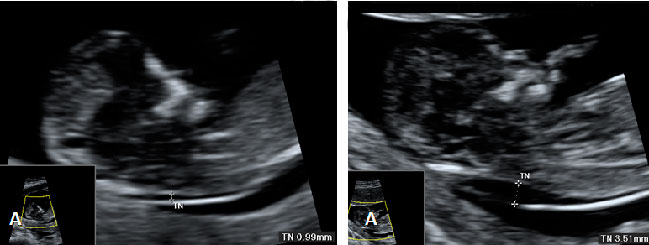

Ecografía Embarazo 2D y 3D Semana 12 - PLIEGUE NUCAL

Ecografía Embarazo 4D Semana 12 - PLIEGUE NUCAL